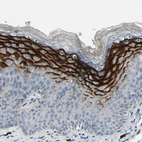

Immunohistochemistry analysis in human tonsil and kidney tissues using HPA009067 antibody. Corresponding SPINK5 RNA-seq data are presented for the same tissues.